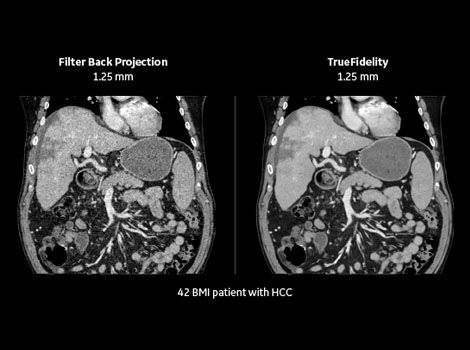

GE proprietary Deep Learning Image Reconstruction is the first AIpowered CT image reconstruction technology. It features a deep neural network (DNN) that can discern noise from signals and intelligently suppress the noise without impacting anatomical and pathological structures.

The resulting TrueFidelity CT images have superb high contrast spatial resolution and low contrast detectability, without impacting Hounsfield unit accuracy.

Revolution CT ES’ outstanding performance in resolution and soft-tissue imaging has the potential to benefit precise target delineation and organ-at-risk (OAR) contouring.

Deep-Learning-Image-Reconstruction-TrueFidelity-CT-Images-with-text